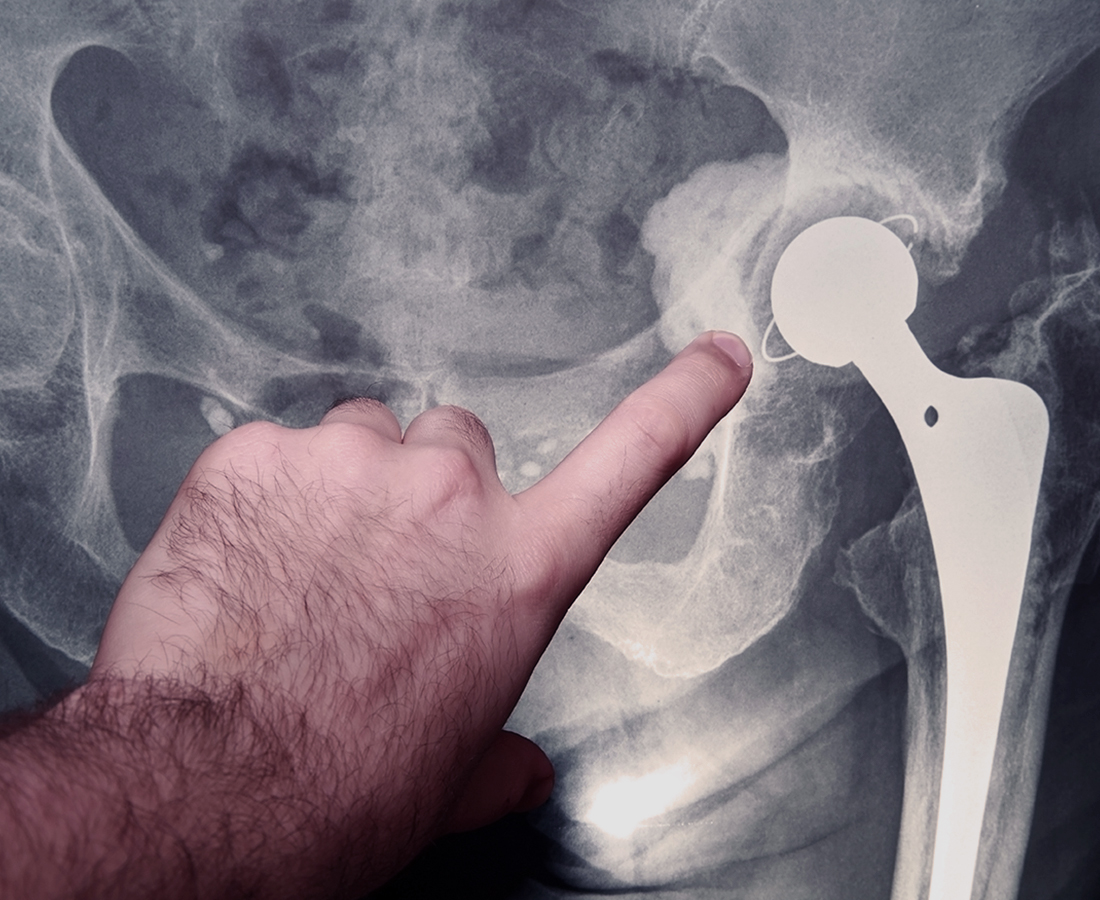

A la suite de la rupture de la tête fémorale d’une prothèse de hanche posée le 23 février 2006, mise en évidence par une radiographie pratiquée le 28 décembre 2006, le patient a subi une intervention, le 4 janvier 2007, afin que soient retirés les débris de la tête céramique et mise en place une nouvelle tête en métal.

Comme le rappelle la Cour de cassation, après avoir écarté, en se fondant sur le rapport d’expertise, l’éventualité que la rupture de la prothèse soit imputable à un surpoids du patient, à une chute ou un comportement inadapté de sa part ou encore à la technique opératoire et au matériel choisi, la Cour d’appel a retenu que cette rupture était intervenue dans un très court délai après la pose de la prothèse.

Sans inverser la charge de la preuve et en s’en tenant à la simple imputabilité du dommage à la rupture de la prothèse, elle a pu en déduire que celle-ci ne présentait pas la sécurité à laquelle le patient pouvait légitimement s’attendre et était défectueuse.

Par ailleurs, dès lors qu’elle a constaté que la rupture de la prothèse initiale était à l’origine non seulement de l’opération de reprise mais aussi de tous les actes chirurgicaux subséquents et des dommages successifs qui en ont résulté pour le patient, la Cour d’Appel n’a pu qu’en déduire que la responsabilité du producteur était engagée au titre de l’ensemble de ces dommages.

Le producteur sera donc tenu d’indemniser l’ensemble des conséquences imputables à la rupture précoce de la prothèse de hanche.